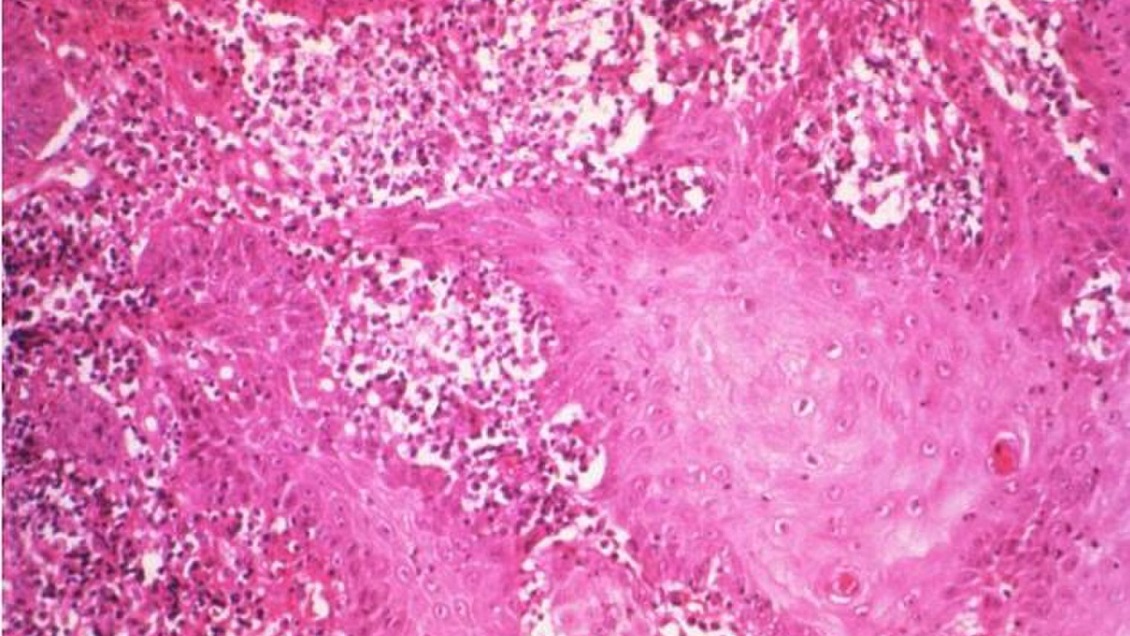

La bacteria, llamada también granuloma inguinal, devora los genitales mediantes úlceras que producen que la piel de la ingle se consuma a sí misma.